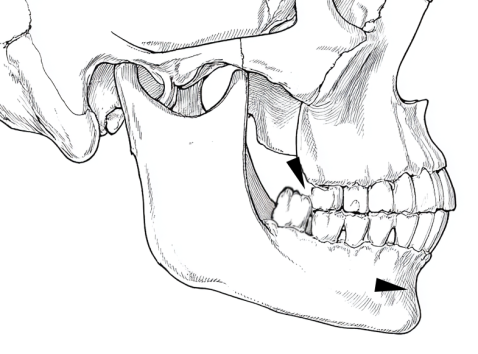

10.親知らずが深いところまで根を張っている場合、何らかの外力がそこに加わると、あごの骨折が起こることもあります

親知らずがあごの中にもぐっていると、その分、あごの骨は厚みが薄くなります。親知らずがある所をぶつけたりすると、下顎が骨折することがあります。